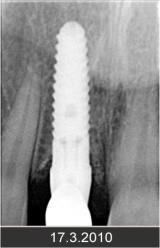

Zavedení implantátů do kosti je většinou ambulantní chirurgický výkon, srovnatelný s vytržením zubu a většinou se provádí v lokální anestézii. Ve výjimečných případech je možné použít i analgosedaci či celkovou narkózu. Operaci provádí zubní lékař-implantolog při dodržení všech podmínek sterility pro operaci. Nástroje pro tuto operaci jsou konstruovány tak, aby výkon byl šetrný vůči kosti a zavedení implantátu bylo provedeno ve velmi krátké době. Díky kvalitní anestézii je výkon nebolestivý. Aby byl pooperační otok co nejmenší, je potřeba operovanou oblast chladit, dle poučení ošetřujícího lékaře. Lékař také ordinuje podle potřeby léky na bolest, případně antibiotika.

Průměrná doba hojení implantátů před provedením definitivního protetického ošetření je 3-4 měsíce, v případech, kde je nutné doplnit chybějící kost (různé metody, postupy a materiály) – tzv. augmentace) se může doba hojení prodloužit na 8-12 měsíců. S tím je pacient vždy předem seznámen svým lékařem.